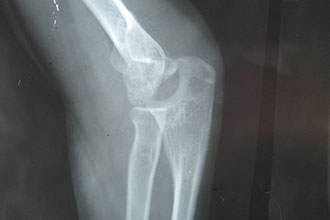

骨裂比骨折更容易恢复?医学上其实并没有骨裂一词科普中国-乐享健康 2019-04-28 作者:路遥 |

文字:中国人民解放军总医院第一附属医院骨科医生路遥